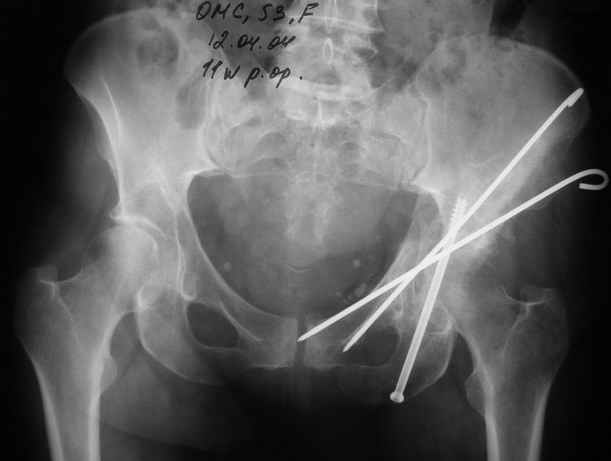

Уважаемые коллеги,Мужчина 36 лет от роду попал в ДТП 24.08.04 Рентгенограммы в приложении.

Диагноз- перелом с вовлечением таза, разрыв правого сакро-илиак сочленения vertical shear injury, перелом крыла подвздошной кости?, перелом ацетабулум Т type или Both column?, перелом шейки бедра, перелом проксимального отдела бедра.

перелом крыла правой подвздошной кости, перелом обеих колонн вертлужной впадины, двусторонний перелом лонных костей (С2.2) повреждение передних связок правого крестцово-подвздошного сочленения,

ипсилатеральный перелом шейки и диафиза бедра.

12.04.04